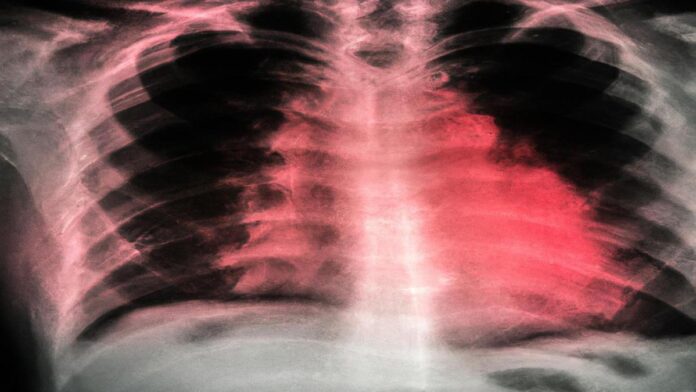

Si no se trata de manera adecuada, la tisis puede causar insuficiencia respiratoria y ser una amenaza mortal. El diagnóstico de la tisis se realiza a través de diversos métodos: la prueba cutánea de la tuberculina, que comprueba si alguien ha estado en contacto con la bacteria de la tuberculosis; la prueba sanguínea, que también verifica la presencia de la bacteria; y la radiografía de tórax, que se utiliza para detectar anormalidades en los pulmones producidas por la enfermedad.